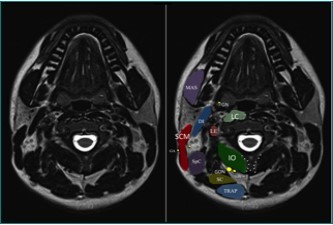

The largest of the three occipital nerves, the GON, arises from the dorsal root ganglion (DRG) of C2, running inferiorly between the arch of C1 (atlas) and the lamina of C2 (axis), lateral to the lateral atlanto-axial (AA) joint and deep to the inferior oblique capitus (IOC) muscle. The GON then curves medially and cephalad over the IOC Figure 1. As the GON travels cephalad up the neck, it travels over the posterior surface of the IOC to pierce the semispinalis capitis muscle, deep to the trapezius muscle, Figure 2 onto the posterior skull through a muscular sling formed by the aponeurosis of the sternocleidomastoid muscle (SCM) and the trapezius muscle at the skull attachment (the conjoined tendon) Figure 3. where it is joined laterally by the occipital artery. The GON can be found at this point lying in a palpable groove, immediately medial to the occipital artery and lateral to occipital prominence (the inion) Figure 1. There are several areas of potential entrapment of the GON

Figure 1.MRI anatomy of the upper cervical region. DI = digastric muscle; IO = inferior oblique muscle; LC = longus colli muscle; LE = levator scapulae muscle; MAS = masseter muscle; SC = semispinalis cervicis muscle; SCM = sternocleidomastoid muscle; SpC = splenius capitis muscle; TRAP = trapezius muscle; GA = great auricular nerve; GON = greater occipital nerve; GN = glossopharygeal nerve. LON = lesser occipital nerve; TON = third occipital nerve. Note the bifid spinous process of C2. (Image courtesy of Andrea Trescot, MD Clinical presentation

MRI anatomy of the upper cervical region. DI = digastric muscle; IO = inferior oblique muscle; LC = longus colli muscle; LE = levator scapulae muscle; MAS = masseter muscle; SC = semispinalis cervicis muscle; SCM = sternocleidomastoid muscle; SpC = splenius capitis muscle; TRAP = trapezius muscle; GA = great auricular nerve; GON = greater occipital nerve; GN = glossopharygeal nerve. LON = lesser occipital nerve; TON = third occipital nerve. Note the bifid spinous process of C2. (Image courtesy of Andrea Trescot, MD Clinical presentation